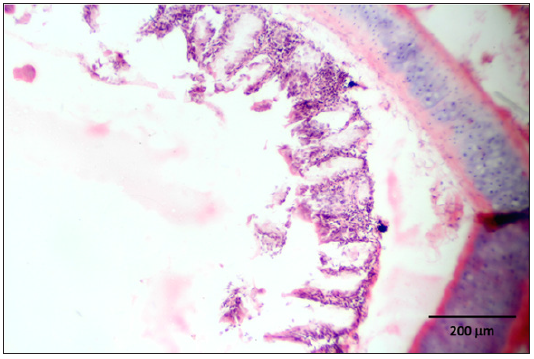

Stained slides from trachea and CAMs were screened under the light microscope. CAMs collected from cases 1 and 3 were congested, hemorrhagic and edematous (Figure 3) as compared to normal (Figure 2). The CAMs collected from cases 1 and 3 were heavily infiltrated with lymphocytes, mononuclear cells (Figure 4 & 5) and many of heterophils with congestion and haemorrhages (Figure 6 & 7). Numerous syncytial cells were also presence in CAMs with intranuclear inclusion bodies in these cells (Figure 8, 9 & 10). Some cells showed presence of intranuclear inclusion body pressing the nucleic material to the periphery of the nucleus (Figure 11). Tracheal samples showed sloughing of the mucosa of the trachea with inflammation (Figure 12) with destruction of the tracheal mucosa due to necrosis and presence of intra-nuclear inclusions within a syncytial cell (Figure 13).

Figure 12: Sloughing of the mucosa of the trachea with inflammation.

Figure 13: Destruction of the tracheal mucosa due to necrosis and presence of intranuclear inclusions within a syncytial cell.

The diagnosis by histopathology is considered a valid and relatively rapid test for ILT [23]. Multinucleated cells (Syncytia) formation and intranuclear inclusion bodies are considered pathognomonic lesions for the diagnosis of ILT [24-27]. Microscopic changes vary according to the stage of the disease. Early microscopic changes in tracheal mucosa include the loss of goblet cells and infiltration of the mucosa with inflammatory cells. As the viral infection progresses, cells enlarge, lose cilia, and become edematous. Syncytial cells are formed and lymphocytes, histiocytes and plasma cells migrate into the mucosa and submucosa. Later, cell destruction and desquamation result in a mucosal surface either covered by a thin layer of basal cells or lacking any epithelial covering. Inclusion bodies are generally present for a few days at the early stage of infection before epithelial cells die [28], but they may be present for only 3-5 days after infection. In severe cases, most infected cells are detached from the tracheal lining [6]. In the current study, intranuclear inclusions were observed in tracheal epithelium along with necrosis and sloughing of the cells. These lesions were absent in some tracheal samples. This may be due to the delay of sample collection from trachea for histopathology. These kinds of lesions are observed in many other respiratory diseases, especially infectious bronchitis, avian influenza and Newcastle disease. In this way, lesions induced by ILT virus, such as hypertrophy and hyperplasia of goblet cells, are similar to those observed following infection with velogenic viscerotrope strains of Newcastle disease virus [29]. Besides, differential diagnosis might be complicated by high frequency of bacterial secondary infections. In the current study, histopathology revealed lesions of ILT in 2 out of 4 outbreaks of suspected ILT infections with suspicion of two other respiratory diseases (infectious bronchitis and Newcastle disease). However, we have not attempted to isolate and diagnose other viral pathogens that may accompany ILTV infection. Samples collected from chickens of the cases 1 and 3 had edema, hemorrhages and syncytia with intranuclear inclusion bodies associated with the chorioallantoic membrane (CAM) allowing confirmatory histopathology diagnosis. Hemorrhage may occur in cases of severe epithelial destruction and desquamation and edematous changes was observed with exposure and rupture of blood capillaries [17].